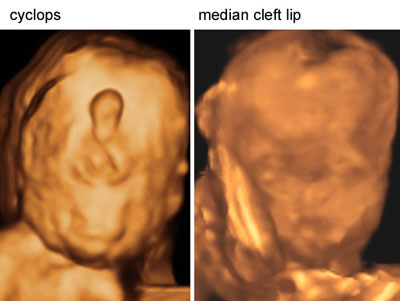

Facial anomalies with holoprosencephaly

Click the image to magnify it

Legend:Facial anomalies with holoprosencephaly

Reference(s):Blaas HG, Eriksson AG, Salvesen KA, Isaksen CV, Christensen B, Møllerløkken G, Eik-Nes SH. Brains and faces in holoprosencephaly: pre- and postnatal description of 30 cases. Ultrasound Obstet Gynecol 2002;19(1):24–38. PubMed PMID: 11851965.

Blaas HG. Holoprosencephaly at 10 weeks 2 days (CRL 33 mm). Ultrasound Obstet Gynecol 2000;15(1):86–7. PubMed PMID: 10776022.

Blaas HG, Eik-Nes SH, Vainio T, Isaksen CV. Alobar holoprosencephaly at 9 weeks gestational age visualized by two- and three-dimensional ultrasound. Ultrasound Obstet Gynecol 2000;15(1):62–5. PubMed PMID: 10776015.